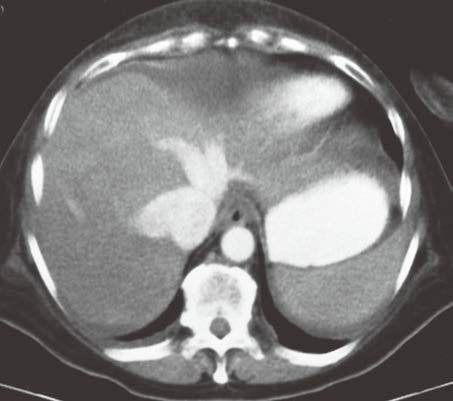

| 脂肪浸润(图1〜图 3) | 肝脏密度弥漫性减低。在肝脏脂肪变的低密度背景下,门静脉表现为高密度结构(平扫时正常门静脉呈低密度)。 | 由于三酰甘油过度沉积所致,见于肝硬化或其他肝脏疾病。正常肝脏平均CT值不低于脾脏,肝脏脂肪 浸润时CT密度较低。肝硬化引起脂肪浸润,伴有肝右叶萎缩,尾状叶体积增大。 |

图1肝硬化患者的肝内脂肪浸润